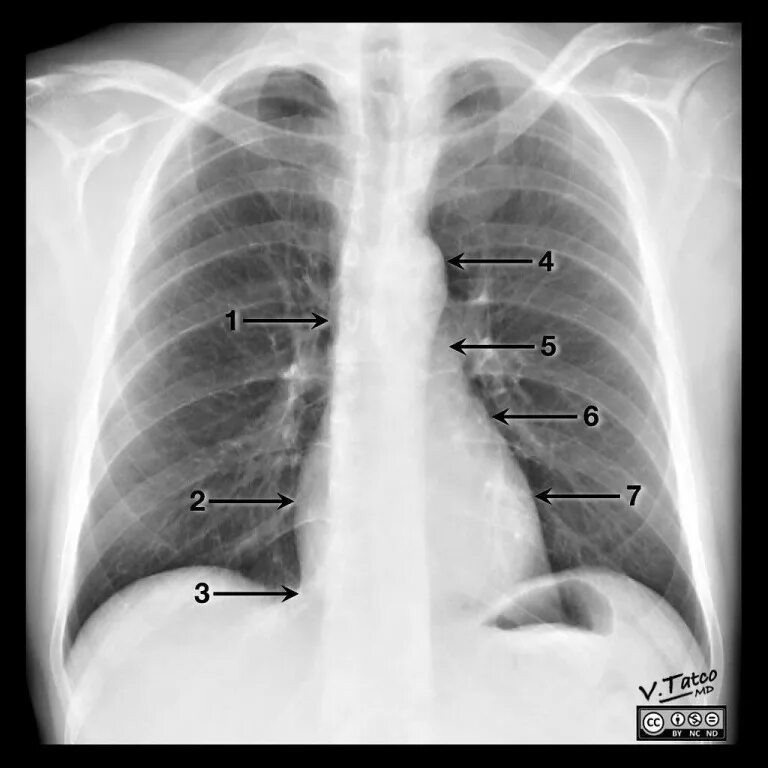

Как прочитать снимок